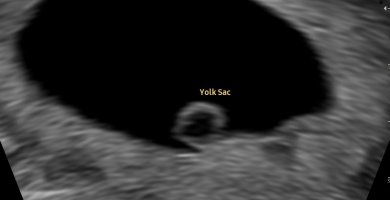

Foreløpig satt tilbake fra 6+4 til 6+2